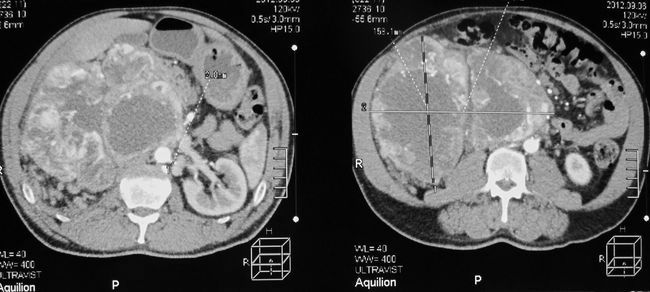

Опухоль правой почки (компьютерная томография с сосудистым контрастированием)

Опухоль правой почки (компьютерная томография)